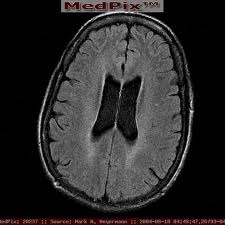

ADHD: CT Studies - University Of New Mexico

ADHD . Overview ADHD • What is ADHD? • Allergies/sensitivities - mimics, doesn’t cause • Brain damage - causes small percentage • Toxic exposure (lead, etc.) - rare cause . • Consider Vyvanse if risk of abuse or diversion . ADHD ... Retrieve Doc